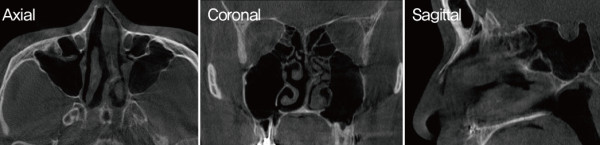

![]()

수술 전 CT. 비밸브 협착을 보였다. 비익연골의 내전과 비중격 미단 변형으로

인한 좌측 비밸브 협착이 확인되었다. 상악수술 후 삽입된 핀이 비골 바닥

부분에 산재되어 있다.

이러한 소견은 이전 양악수술에 의한 결과일 가능성이 있다. 또한 비익연골의 내전과 비중격 미단부의 변형으로 인한

좌측 비밸브 협착이 관찰되었다.